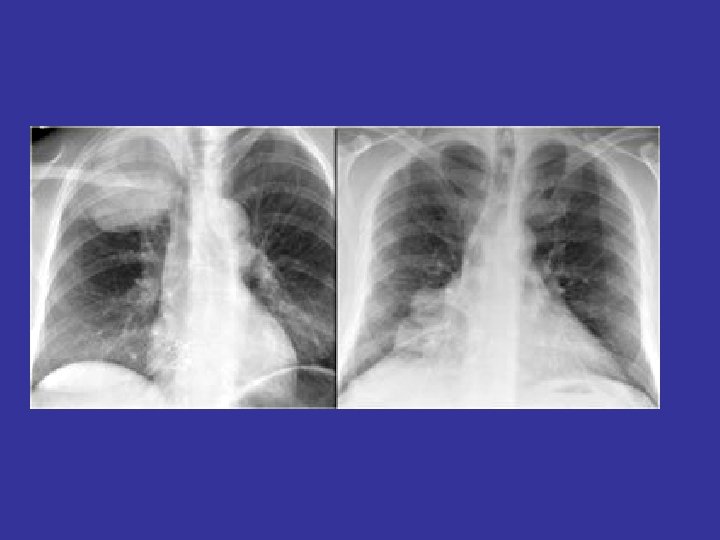

Beware of tunnel vision

The lateral chest film our best friend • Find abnormalities on the frontal film

The lateral chest film our best friend • Find abnormalities on the frontal film • Confirm abnormalities suspected from frontal film • Don’t be afraid to look at it